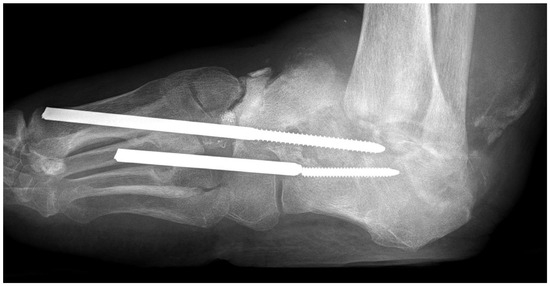

4.1. Skeletal Problems

| skeletal changes | rare | frequent (Charcot foot) |

7. Revascularization